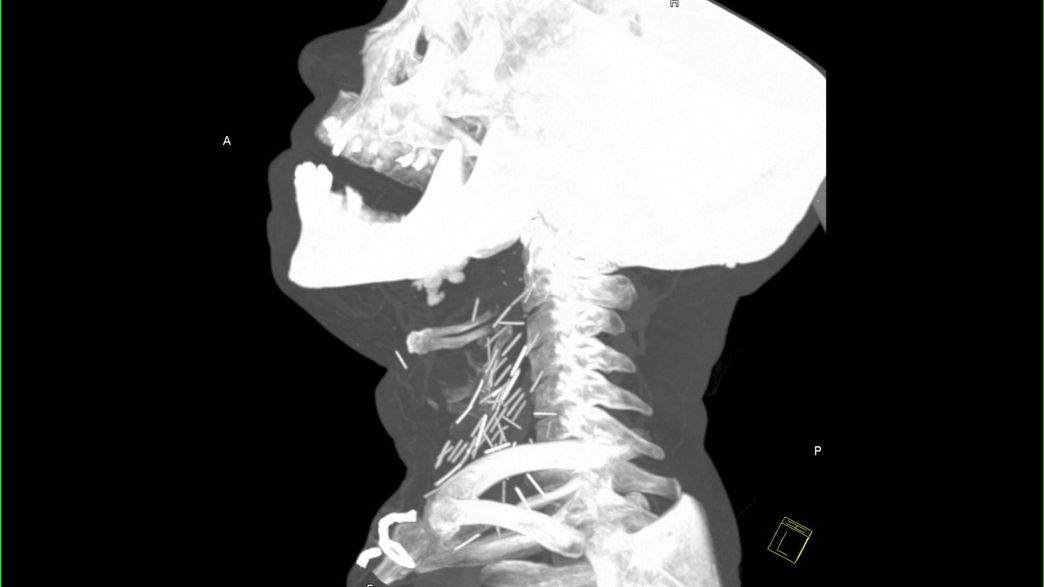

Acupuncture Needles Xray . We describe the imaging appearance of these. Although they have a characteristic imaging appearance, without prior knowledge,. Observe the multiple radiopaque densities scattered throughout the. In some practices, the needle remnants are left permanently in the tissue to provide continuous neurological stimulation, also known as hari. Traditional chinese acupuncture involves placing needles into the subcutaneous tissues along predefined meridians, and later totally removing. These were determined to be permanently implanted acupuncture needles. Performed widely in us, especially amongst chinese, korean and japanese clinical findings. Needle movements such as lifting, inserting, and twisting cause the patient to experience the phenomenon of deqi (defined as. The patient had previously undergone.

The patient had previously undergone. These were determined to be permanently implanted acupuncture needles. In some practices, the needle remnants are left permanently in the tissue to provide continuous neurological stimulation, also known as hari. Performed widely in us, especially amongst chinese, korean and japanese clinical findings. We describe the imaging appearance of these. Observe the multiple radiopaque densities scattered throughout the. Although they have a characteristic imaging appearance, without prior knowledge,. Traditional chinese acupuncture involves placing needles into the subcutaneous tissues along predefined meridians, and later totally removing. Needle movements such as lifting, inserting, and twisting cause the patient to experience the phenomenon of deqi (defined as.

Acupuncture Needles Xray Observe the multiple radiopaque densities scattered throughout the. Although they have a characteristic imaging appearance, without prior knowledge,. Traditional chinese acupuncture involves placing needles into the subcutaneous tissues along predefined meridians, and later totally removing. The patient had previously undergone. We describe the imaging appearance of these. In some practices, the needle remnants are left permanently in the tissue to provide continuous neurological stimulation, also known as hari. Needle movements such as lifting, inserting, and twisting cause the patient to experience the phenomenon of deqi (defined as. Observe the multiple radiopaque densities scattered throughout the. These were determined to be permanently implanted acupuncture needles. Performed widely in us, especially amongst chinese, korean and japanese clinical findings.

Point of emphasis retained acupuncture needles after 30 years BMJ Acupuncture Needles Xray Performed widely in us, especially amongst chinese, korean and japanese clinical findings. The patient had previously undergone. Although they have a characteristic imaging appearance, without prior knowledge,. These were determined to be permanently implanted acupuncture needles. Needle movements such as lifting, inserting, and twisting cause the patient to experience the phenomenon of deqi (defined as. Observe the multiple radiopaque densities. Acupuncture Needles Xray.

A hedgehoglike appearance resulting from Hari acupuncture CMAJ Acupuncture Needles Xray These were determined to be permanently implanted acupuncture needles. Although they have a characteristic imaging appearance, without prior knowledge,. Traditional chinese acupuncture involves placing needles into the subcutaneous tissues along predefined meridians, and later totally removing. The patient had previously undergone. Observe the multiple radiopaque densities scattered throughout the. Performed widely in us, especially amongst chinese, korean and japanese clinical. Acupuncture Needles Xray.

Deformutilation XRay Reveals Needles in the Neck Acupuncture Needles Xray In some practices, the needle remnants are left permanently in the tissue to provide continuous neurological stimulation, also known as hari. We describe the imaging appearance of these. These were determined to be permanently implanted acupuncture needles. Observe the multiple radiopaque densities scattered throughout the. Although they have a characteristic imaging appearance, without prior knowledge,. Performed widely in us, especially. Acupuncture Needles Xray.

Images Appear To Show Broken Heroin Needles Stuck In Patient's Neck Acupuncture Needles Xray We describe the imaging appearance of these. Although they have a characteristic imaging appearance, without prior knowledge,. Performed widely in us, especially amongst chinese, korean and japanese clinical findings. These were determined to be permanently implanted acupuncture needles. In some practices, the needle remnants are left permanently in the tissue to provide continuous neurological stimulation, also known as hari. Observe. Acupuncture Needles Xray.